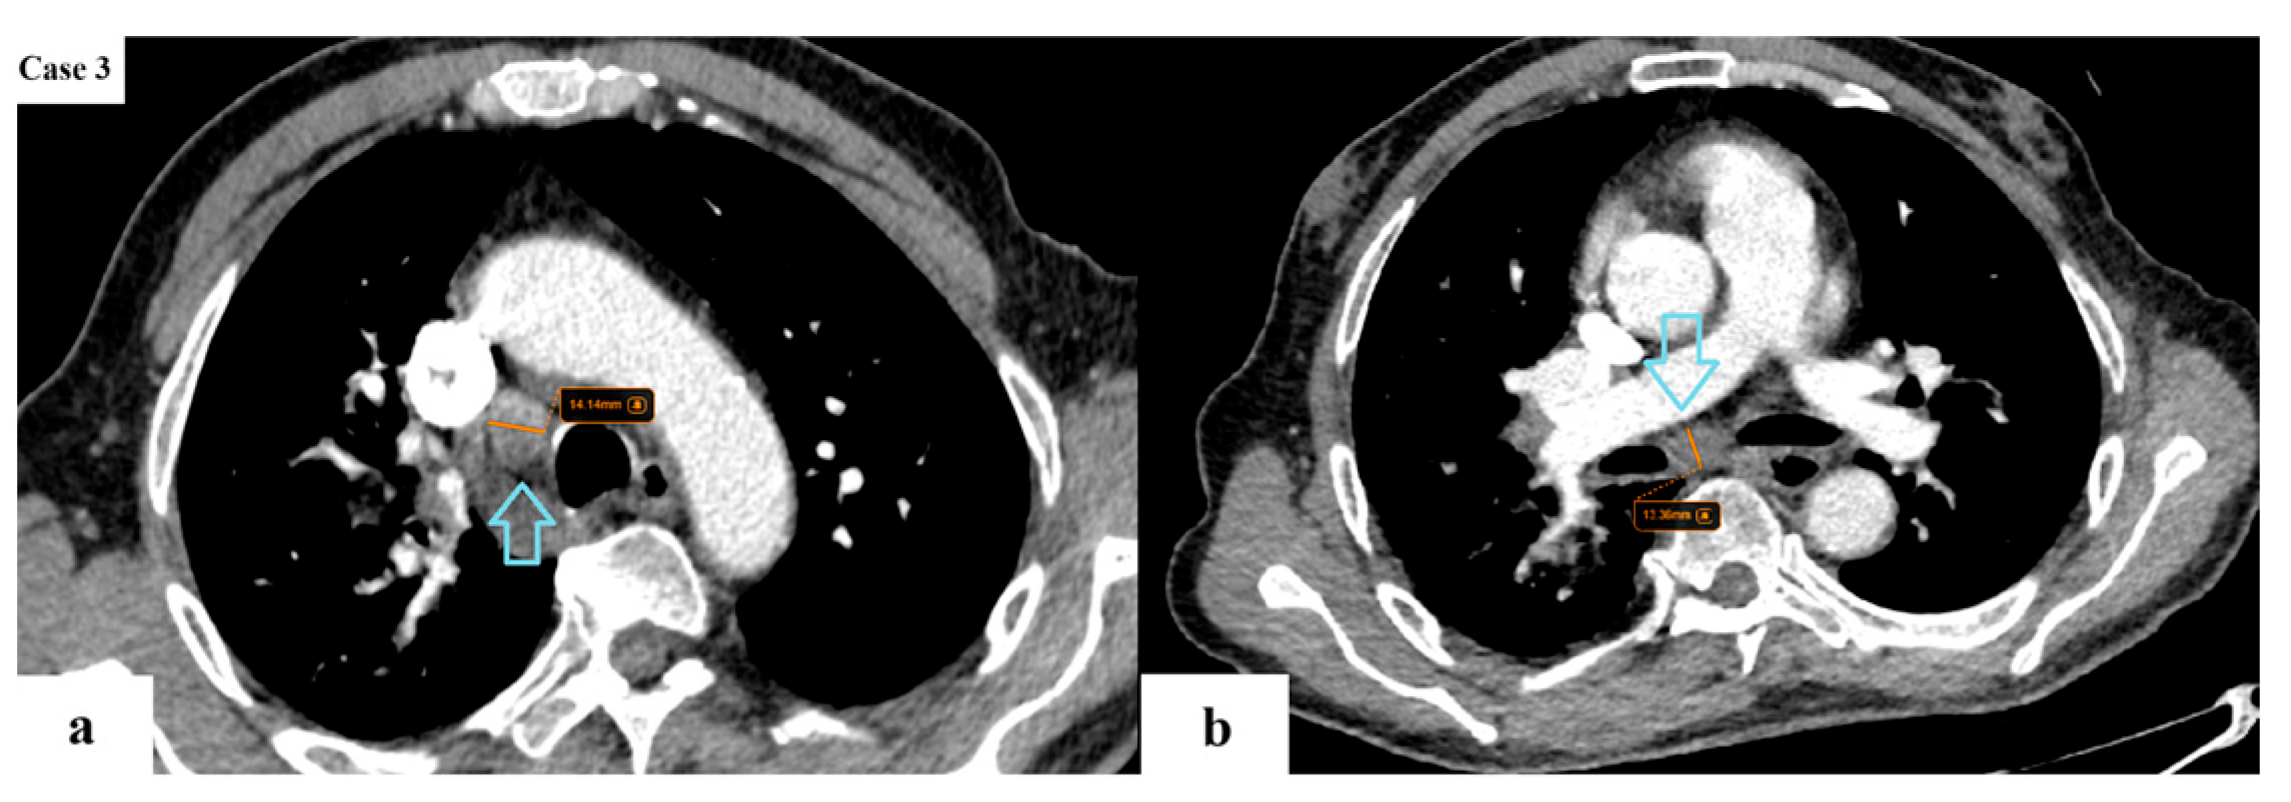

2.2. Data Collection and Imaging Evaluation

2.3. Staging Procedures

- N descriptor: subdivision of N2 disease into single-station (N2a) and multi-station (N2b);